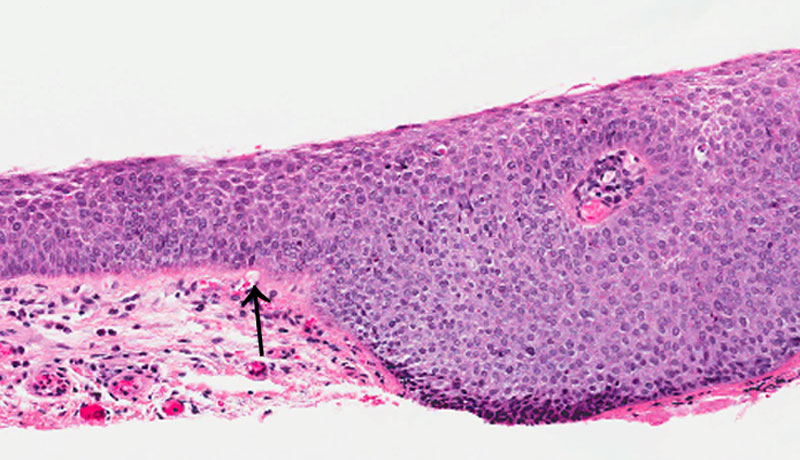

DISEASE: Conjunctival intraepithelial neoplasia

HISTOLOGY FEATURES: Atypical epithelial cells, hypercellular and basophilic. Thickened epithelium. Mitotic figures present. Transition from normal to neoplasia is abrupt.